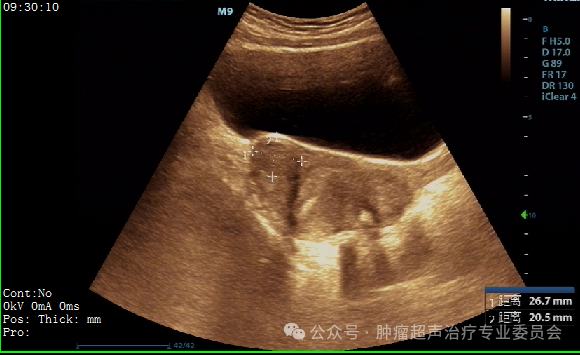

治疗前妇科彩超检查

子宫前壁见一个大小约44×27mm的低回声团;

后壁见一个大小约49×33mm的低回声团,6型。

子宫后壁肌瘤缩小至29*25mm,子宫前壁肌瘤

缩小至26*20mm。较治疗前缩小达40%。